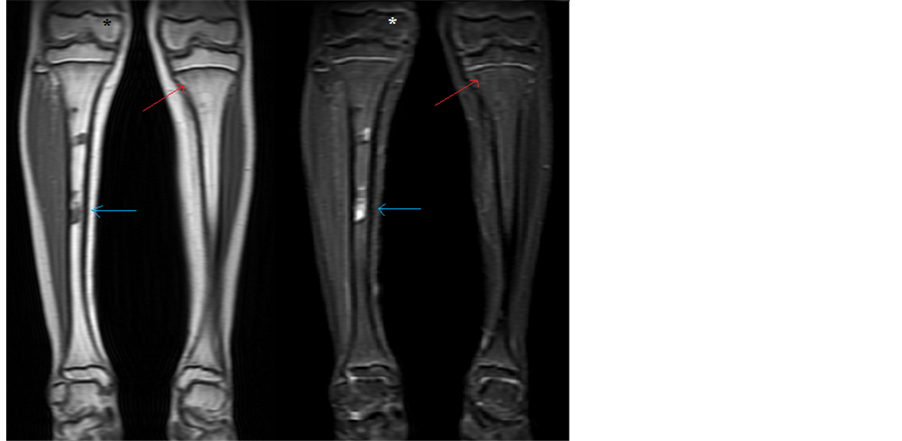

Currently, the patient is on maintenance chemotherapy. A repeat whole body PET/CT scan demonstrated no new evidence of abnormal activity to suggest disease recurrence or progression. A repeat MRI of bilateral legs showed therapeutic response to chemotherapy with decrease in size of bilateral tibial lesions (Figure 6).

Figure 6. Repeat MRI shows persistence of the periosteal defect in the right tibial shaft, as denoted by the blue arrow. The T1 hypodensity and STIR hyperintensity in the left tibia have normalized, denoted by the red arrow. The star marks normal signal in the right distal femur.